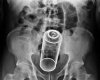

Ludzie to niesamowity gatunek. Potrafią tworzyć niesamowite rzeczy, ale jednocześnie potrafią być równie skretyniali co inteligentni. Mamy dla Was galerię niesamowitych szpitalnych zdjęć rentgenowskich na których uwieczniono człowieka i narzędzie zbrodni. Nigdy nie uwierzycie jakie przedmioty ludzie wkładają sobie w tyłek!